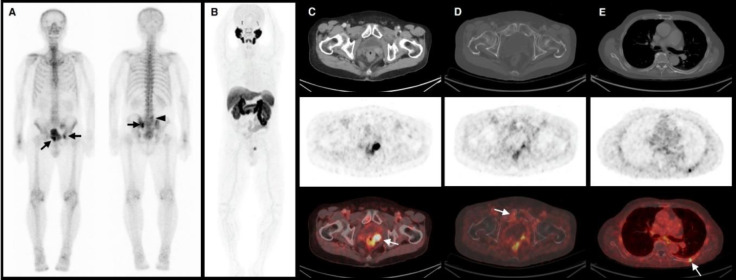

Abstract Image